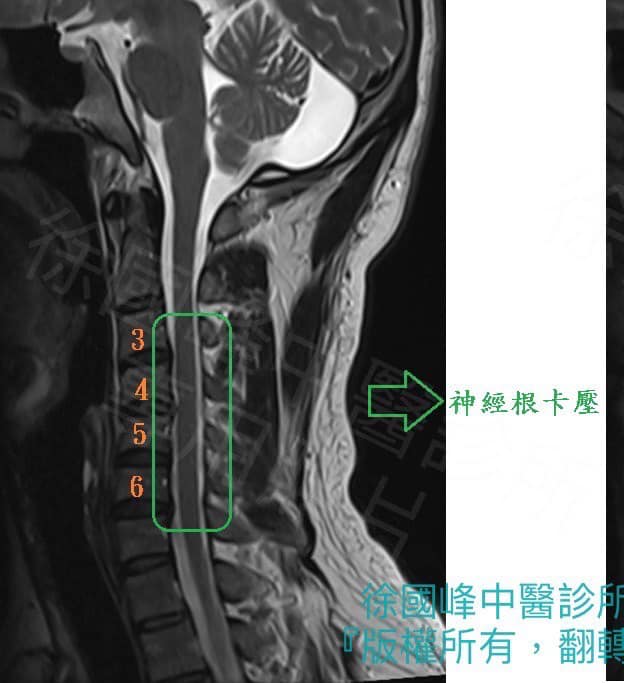

1.C3C4C5頸椎過直

2.C3C4;C4C5;C5C6神經根型頸椎病

3.慢性筋膜發炎疼痛

4椎動脈型頸椎病

直到友人介紹來診所求醫,評估完核磁共振後才發現手腕的痠痛是因為頸椎所引起的,困惱人的耳鳴是頸椎動脈跟椎動脈受壓迫